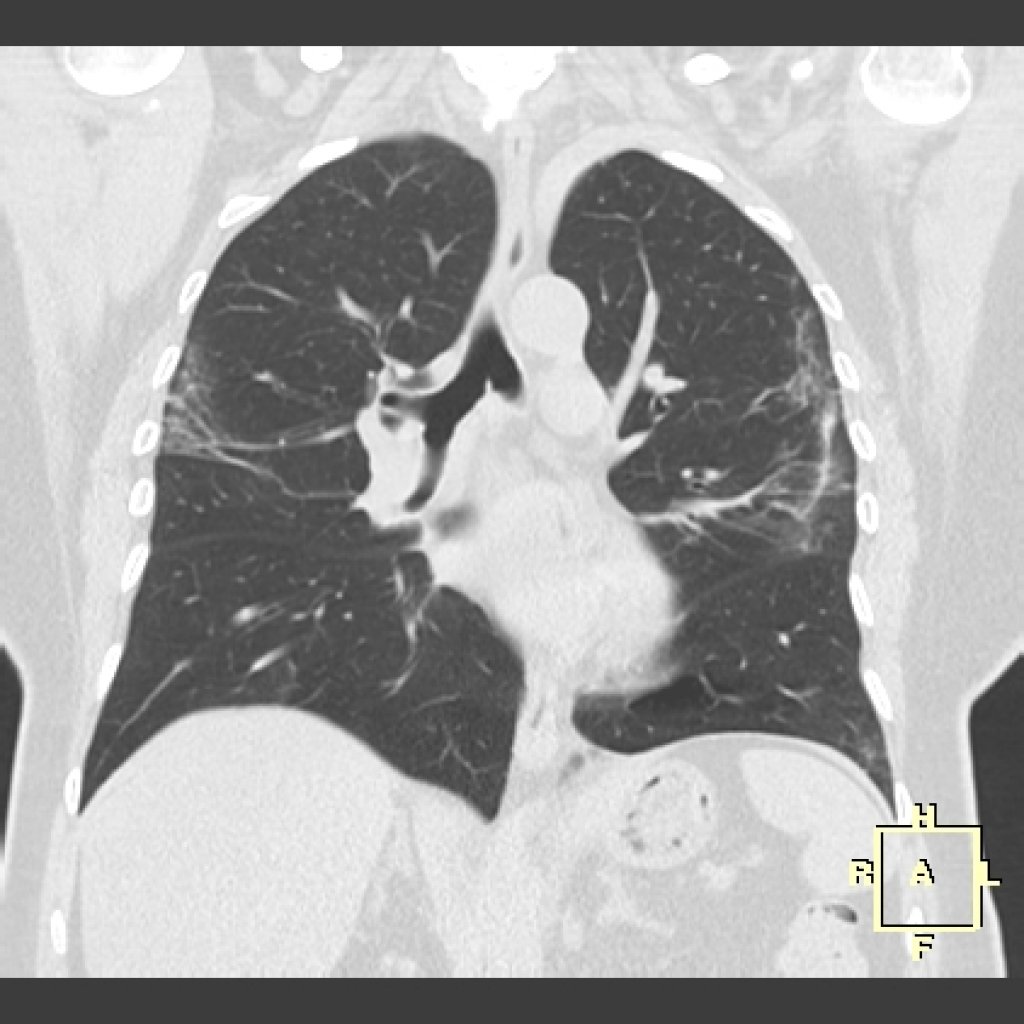

Почніть з терапевта: ослуховування виявляє крепітацію – хруст снігу в легенях. Спирометрія показує рестрикцію – FVC падає, DLCO <40%. КТ високої роздільності (HRCT) – золото: “матове скло”,蜂窝肺, тракційні бронхоектази для IPF.

Біопсія критична для диференціації від саркоїдозу чи раку. Ехо серця, 6-хвилинний тест ходьби оцінюють прогноз. В Україні за протоколом МОЗ 2025 біопсія з кількох часток – стандарт для ІЛФ.

Рання діагностика множить шанси: від симптомів до КТ – менше року, і терапія стартує вчасно.